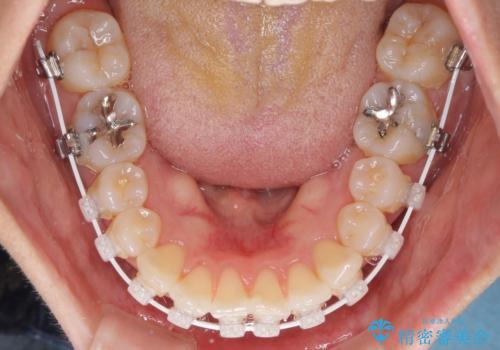

- 矯正装置

- 審美装置

早く治療を終えたいとのことで、ワイヤー装置による矯正治療を行うこととしました。

上顎前歯の叢生が解消されると出っ歯になることが分かっていたので、両側奥歯付近にアンカースクリューを入れ、出っ歯を改善するためのゴムかけを行いました。

ゴムかけを頑張っていただいたので、当初の予定通り、1年強で治療を終えることができました。